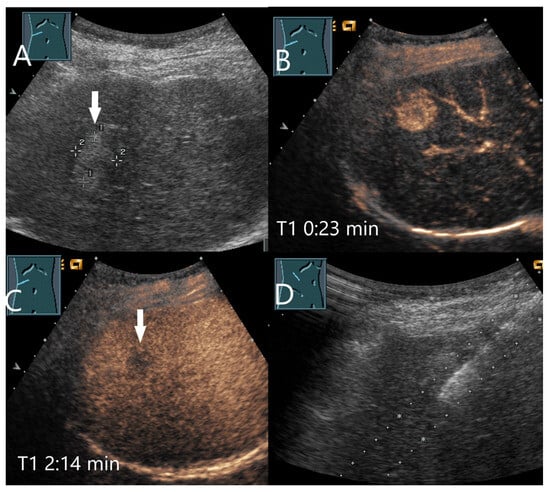

Figure 7.

ß-catenin-mutated HCA. Female patient. Incidental findings of a 19 × 17 mm hyperechoic FLL on B-mode US (arrow) (A). CEUS shows arterial hyperenhancement after 23 s (B). The center is less hyperenhanced. After 2:14 min, the lesion shows a slight washout (arrow) (C). The US-guided biopsy (D) revealed the diagnosis of a ß-catenin mutated HCA.